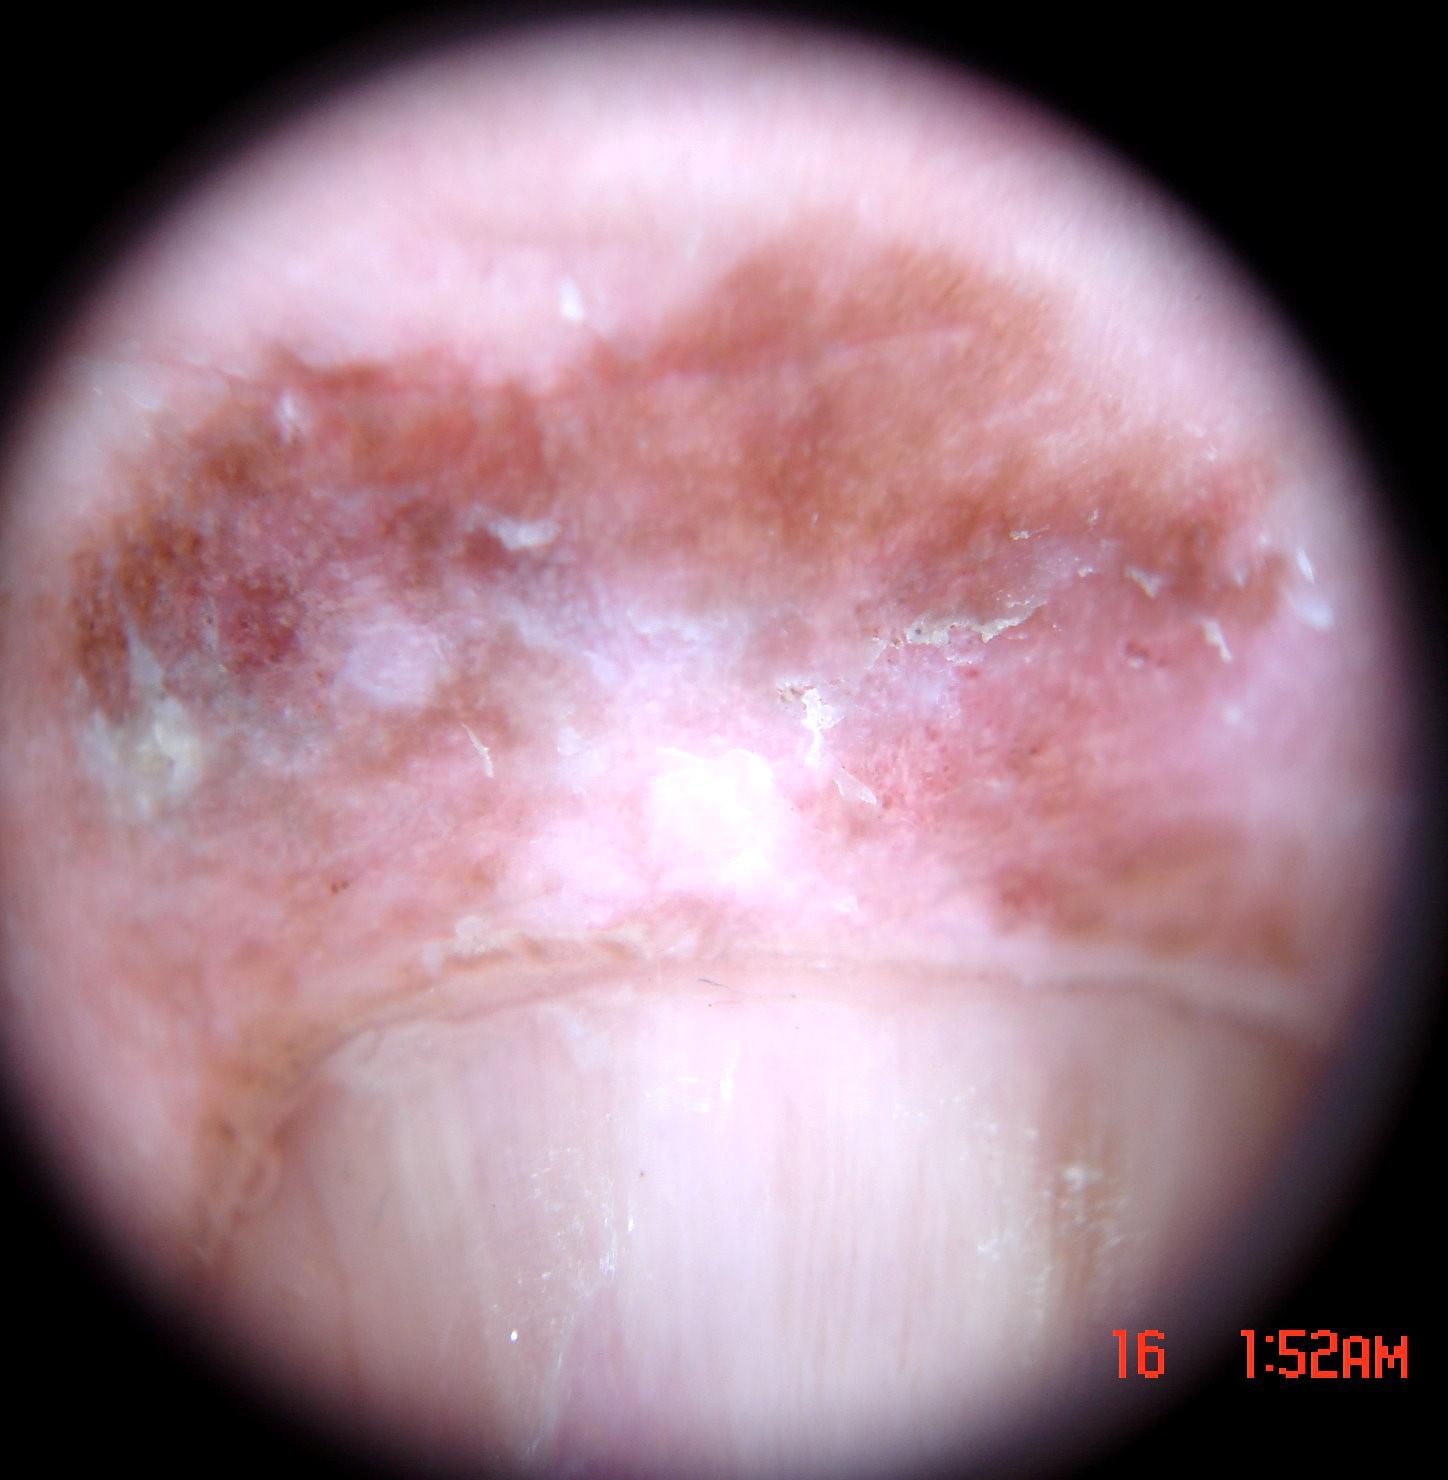

{

"age_approx": 65,

"anatom_site_general": "upper extremity",

"anatom_site_special": "acral NOS",

"concomitant_biopsy": true,

"dermoscopic_type": "non-contact polarized",

"diagnosis_1": "Malignant",

"diagnosis_2": "Malignant melanocytic proliferations (Melanoma)",

"diagnosis_3": "Melanoma in situ",

"diagnosis_confirm_type": "histopathology",

"family_hx_mm": false,

"image_type": "dermoscopic",

"mel_thick_mm": "0.00",

"melanocytic": true,

"patient_id": "IP_3069248",

"personal_hx_mm": false,

"sex": "male"